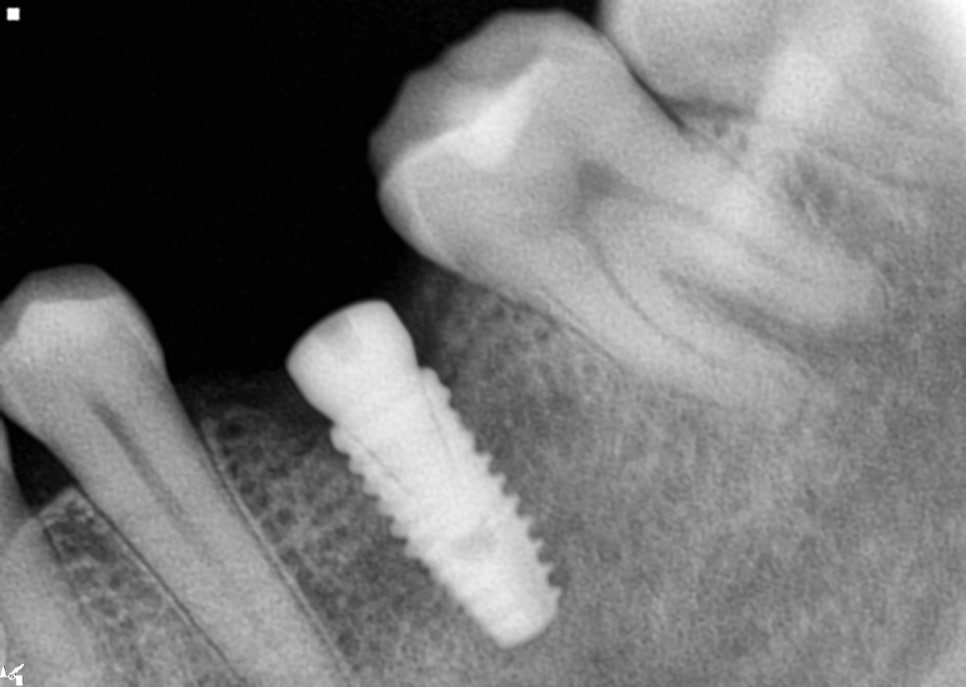

아래쪽 임플란트

아래 왼쪽 첫번째 큰 어금니 부위

왼쪽 아래 첫번째 큰 어금니는

바로 인접한 치아가 앞쪽으로 기울어져

있는것을 확인 할 수 있었습니다.